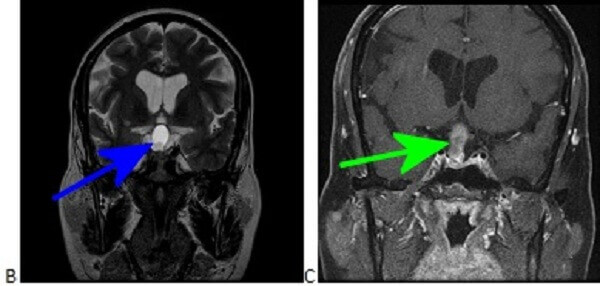

Figure 1B-D: The mass is very T2 hyperintense (B) with a dependent nodule of lower T2 hyperinstensity (blue arrow). Coronal T1 post contrast (C) and pre contrast (D) demonstrate subtle nodular enhancement along the inferolateral margin of the mass (green arrow).